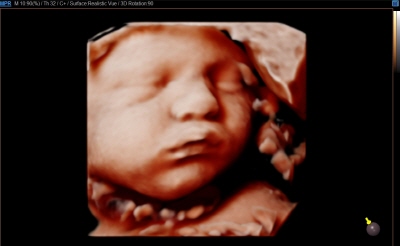

입체 초음파 영상 장비 (삼성 HS50)

초음파 영상에 음영효과를 입혀 입체감 있게 보여주는 기술이 적용된 장비입니다. 태아의 발달과 이상 유무를 자세히 확인하실 수 있습니다.

태아의 초음파 영상은 '세이베베' 서비스를 통해 핸드폰과 PC로 확인하실 수 있습니다.